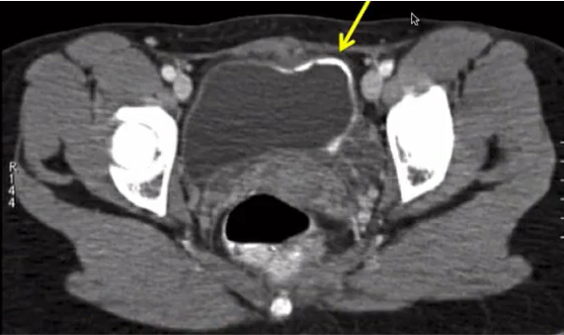

history of schistosomiasis

schistosomiasis